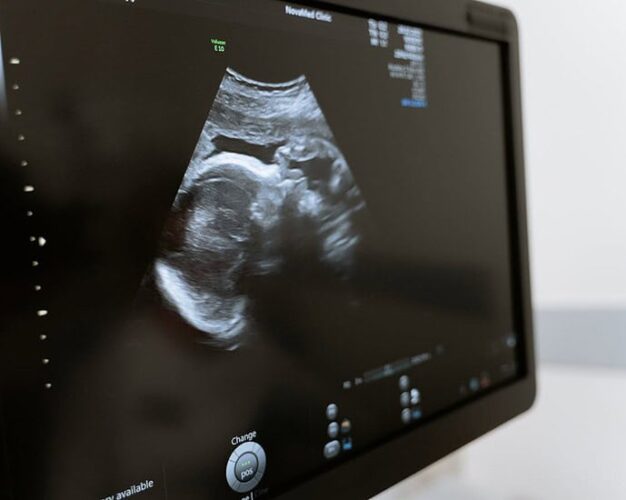

The Dangers of Ultrasound

Article Copyright: Covid Truths Ladies and gentlemen, it’s time to make it clear about the dangers of ultrasound, because this technology is accepted by the antenatal teams all over the world as safe and effective, and the truth is that no long term studies have ever been done to determine the long term effects on the fetus in utero. Sadly, money is the winner over this technology, and not those precious babies in the womb.continue reading…